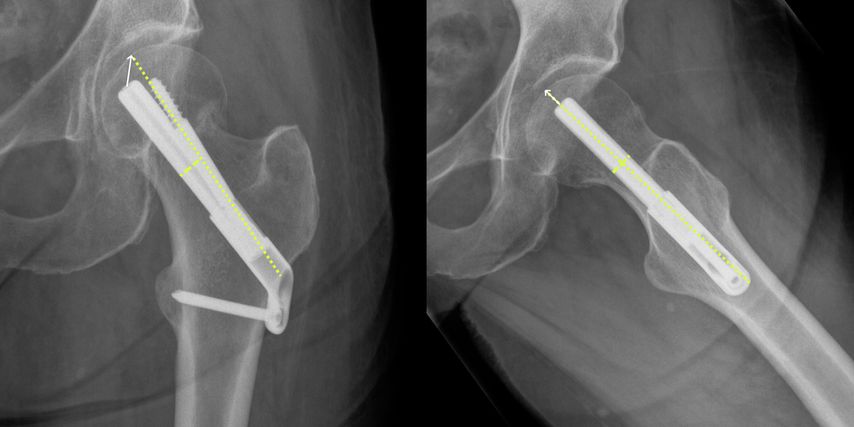

Die Indikationsstellung zur Schenkelhalsosteosynthese erfolgte in 49 Fällen (58,3%) bei Frakturen der Kategorie Garden I. 33 Patient:innen (39,3%) wiesen eine nicht dislozierte Fraktur auf (Garden II). In jeweils einem Fall wurde eine Osteosynthese bei höhergradiger Dislokation im Rahmen eines palliativen Settings unternommen (Garden III: n=1, Garden IV: n=1). Über das gesamte Kollektiv zeigte sich ein Tip-Apex-Abstand (Abb. 3) von 2,12 (±0,63)cm im Mittel. Das radiologische Merkmal war kein Prädiktor für eine Revision (p=0,427).